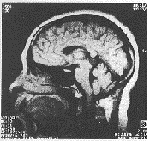

先天性松果体囊肿的MRI表现:①松果体四叠体池内圆形或类圆形囊性病灶,直径0.8~2.3 cm不等,周边有完整包膜。②囊性病灶信号均匀,T1WI显示囊壁为等信号,囊内容物为低信号,T2WI表现为均匀高信号。③注射Gd-DTPA之后,病灶囊壁轻度强化或不强化,内容物未见强化。④中脑导水管及第三脑室无扩大。⑤大脑大静脉流空效应存在(图1~4)。

图3 头颅矢状位T1WI(TR/TE=500/30 ms)。囊壁呈等信号,囊内容物呈低信号,周围有完整包膜,中脑导水管及第三脑室无扩大,大脑大静脉流空效应存在

图4 头颅矢状位T1WI(TR/TE=500/30 ms)。注射Gd-DTPA增强后囊壁轻度强化,囊内容物未见强化